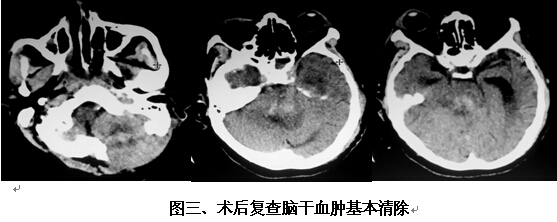

患者男,63歲,因突發(fā)神志不清2小時入院。入院時神志呈淺昏迷狀,頭顱CT提示腦干出血(橋腦、中腦區(qū)域,量約9ml)(見圖一)。神經(jīng)外科鐘三寶主任醫(yī)師查看患者后,分析患者病史、臨床表現(xiàn)及體查,結(jié)合影像學結(jié)果,考慮患者為重癥高血壓性腦干出血,需開顱行腦干血腫清除術(shù)。在發(fā)病后6小時左右,由鐘三寶主任醫(yī)師主刀,帶領(lǐng)李遠志副主任醫(yī)師為患者進行了手術(shù)。根據(jù)Brown兩點定位法則,采取枕下乙狀竇后入路,手術(shù)頭皮切口設計為勾型,骨窗大小約3cm*4cm(見圖二),術(shù)中清除腦干血腫約10ml,手術(shù)非常成功。術(shù)后復查頭顱CT提示腦干血腫基本清除(見圖三)。